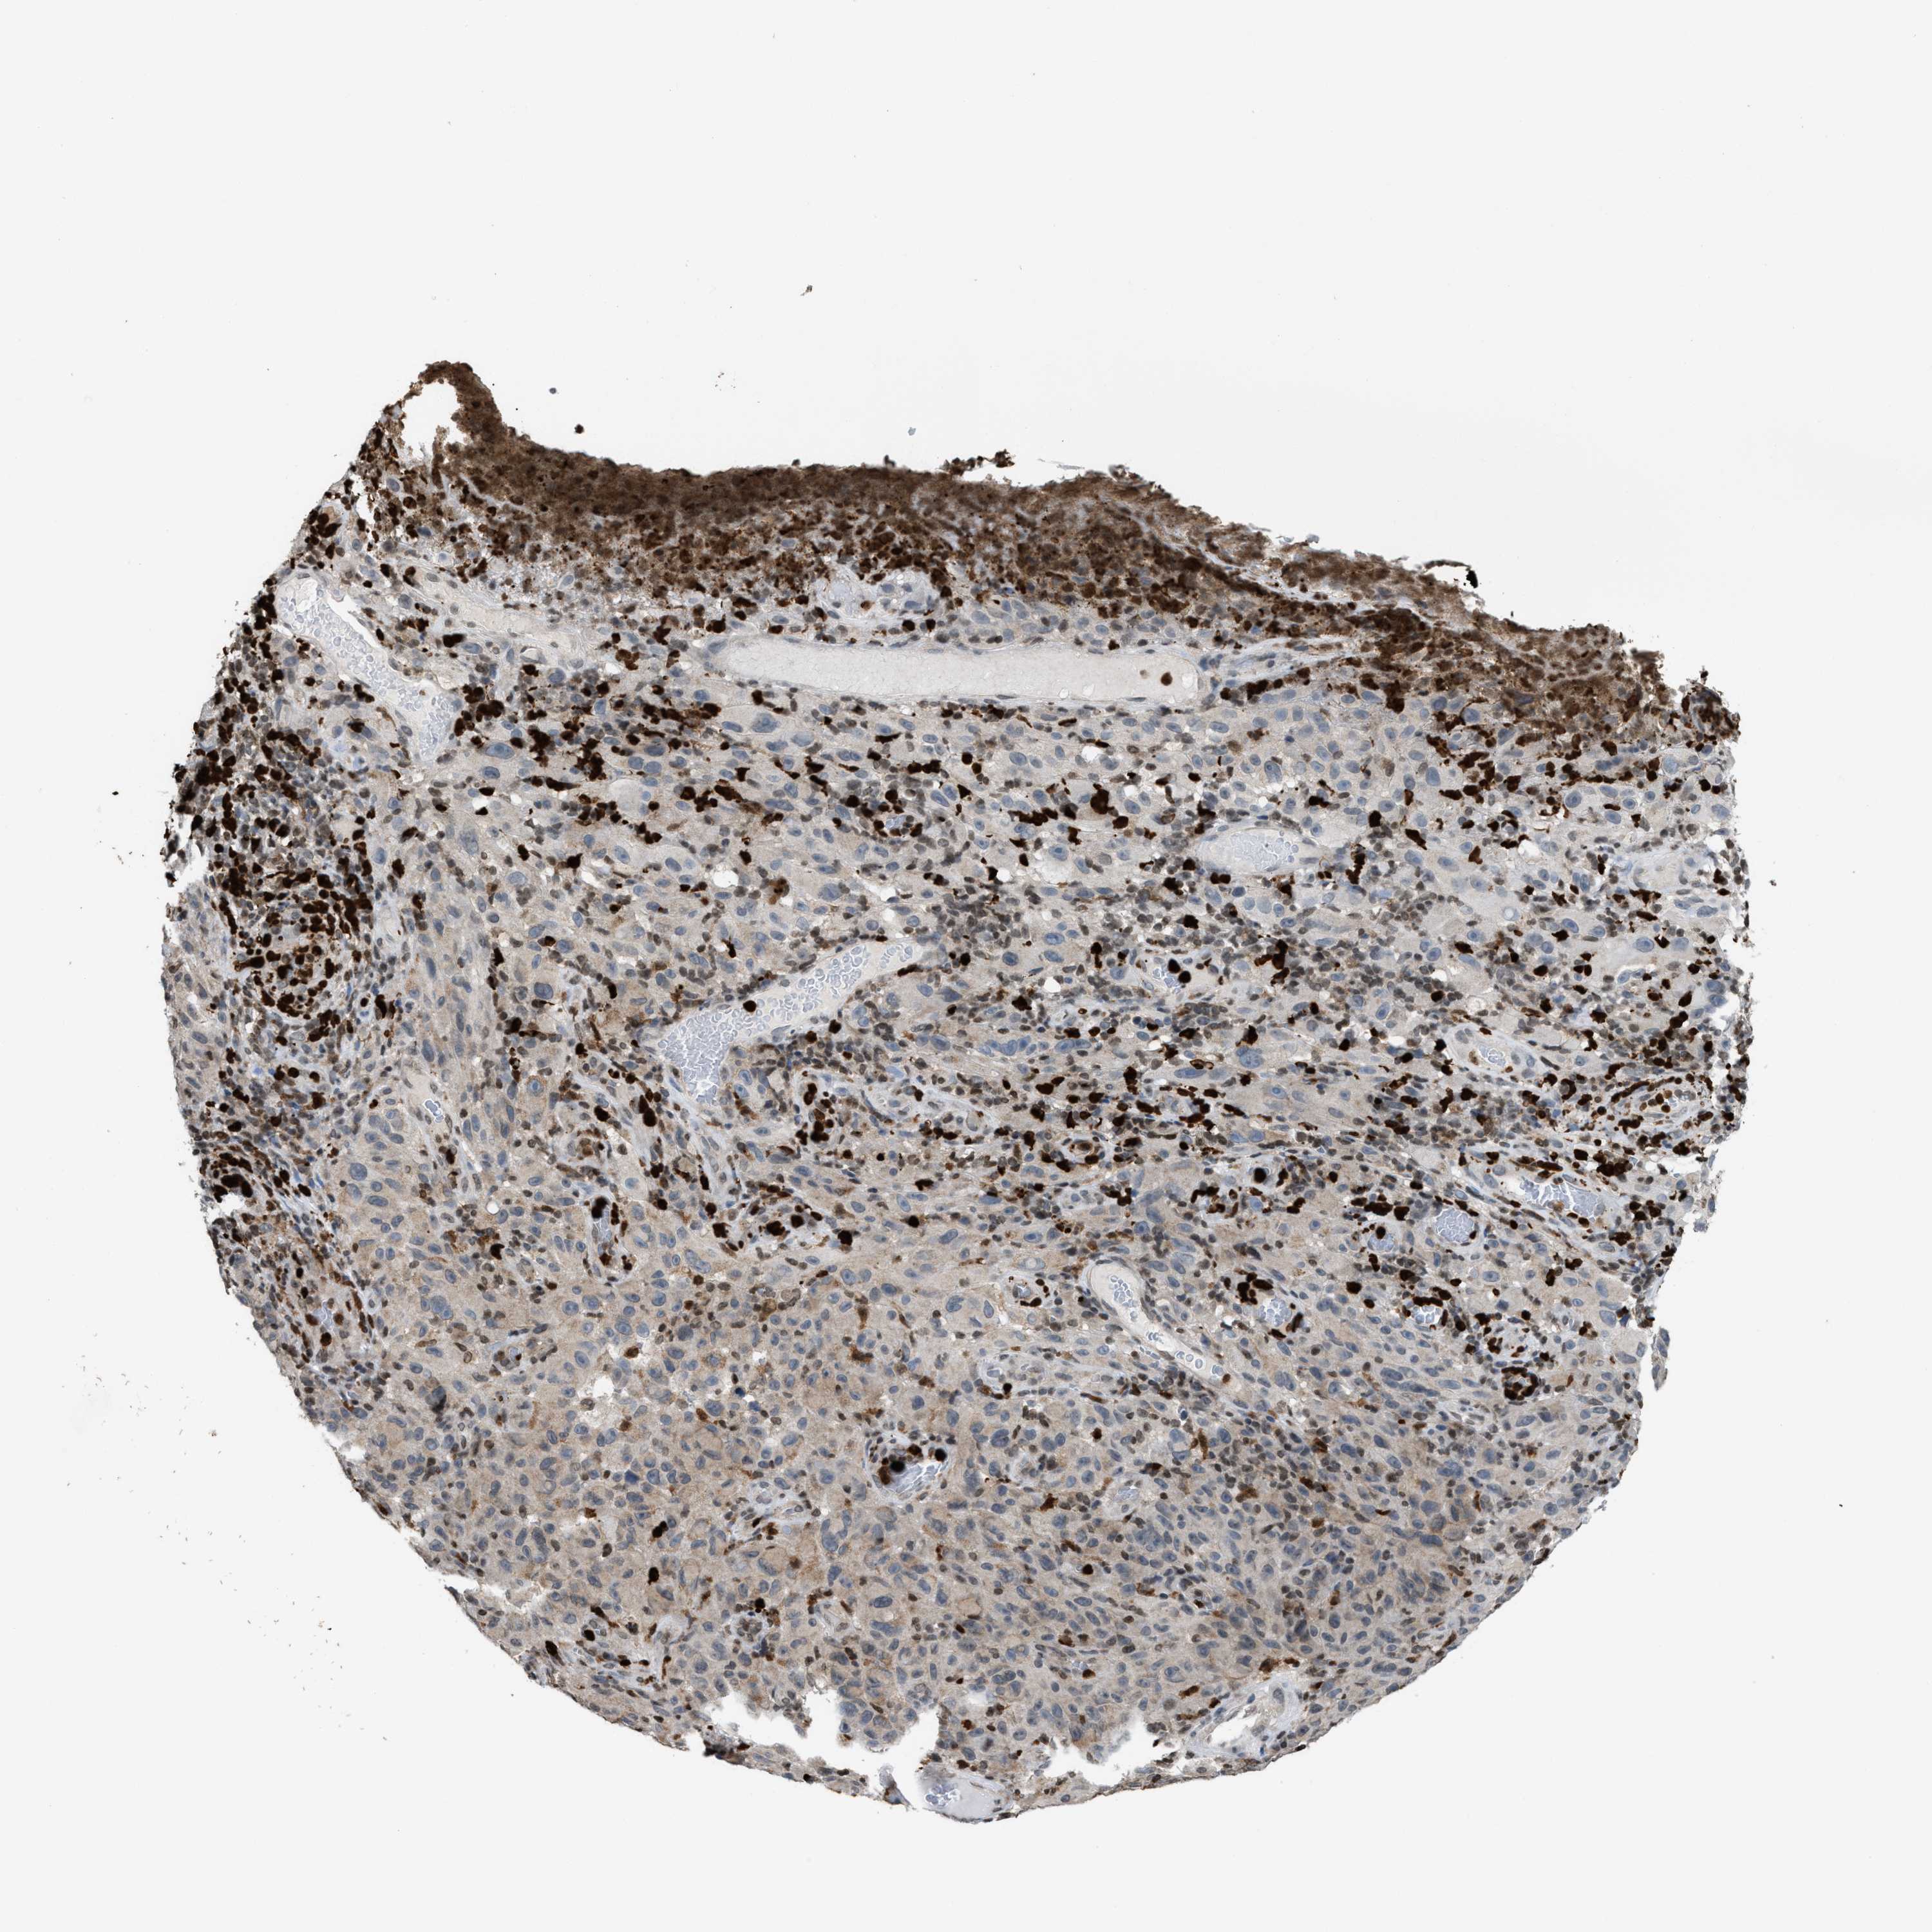

MELANOMA - Protein expressioni

A mouse-over function shows sample information and annotation data. Click on an image to view it in a full screen mode. Samples can be filtered based on level of antibody staining by selecting one or several of the following categories: high, medium, low and not detected. The assay and annotation is described here.

Note that samples used for immunohistochemistry by the Human Protein Atlas do not correspond to samples in the TCGA dataset.

Antibody stainingi

Antibody staining in the annotated cell types in the current human tissue is reported as not detected, low, medium, or high, based on conventional immunohistochemistry profiling in selected tissues. This score is based on the combination of the staining intensity and fraction of stained cells.

Each image is clickable and will lead to virtual microscopy that enables deeper exploration of all samples and also displays staining intensity scores, fraction scores and subcellular localization as well as patient and tissue information for each sample.

Antibody HPA022470

Antibody HPA031079

Staining

High

Medium

Low

Not detected

Intensity

Strong

Moderate

Weak

Negative

Quantity

>75%

75%-25%

<25%

None

Location

Nuclear

Cytoplasmic/membranous

Cytoplasmic/membranous,nuclear

Malignant melanoma, NOS

Malignant melanoma, Metastatic site